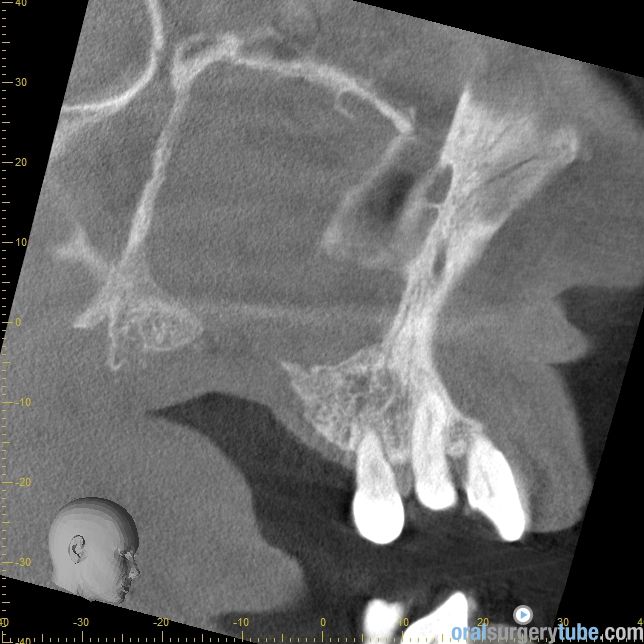

Cierre de comunicación orosinusal con tejido duro y blando